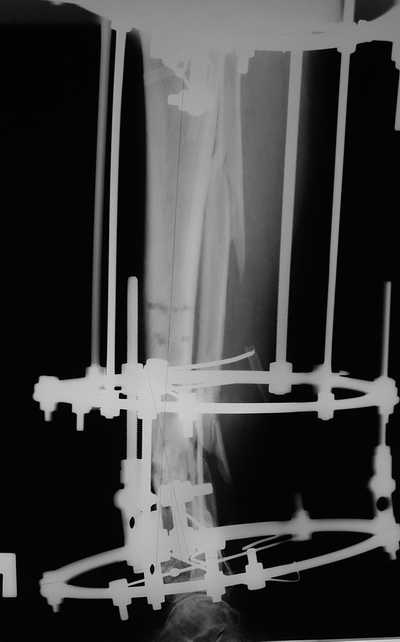

Мужчина, 33 года, резекция б\б кости по поводу остеомиелита после открытого перелома. Стандартная методика билокального остеосинтеза (рис 1 и 2). В конце удлинения выявилось неудовлетворительное взиморасположение перемещенного фрагмента и дистального отломка (рис 3). Планирование (рис 4).

Адаптация отломков гексаподом за 5 дней (рис 5). Замена гексапода на обычные штанги (рис 6 и 7)